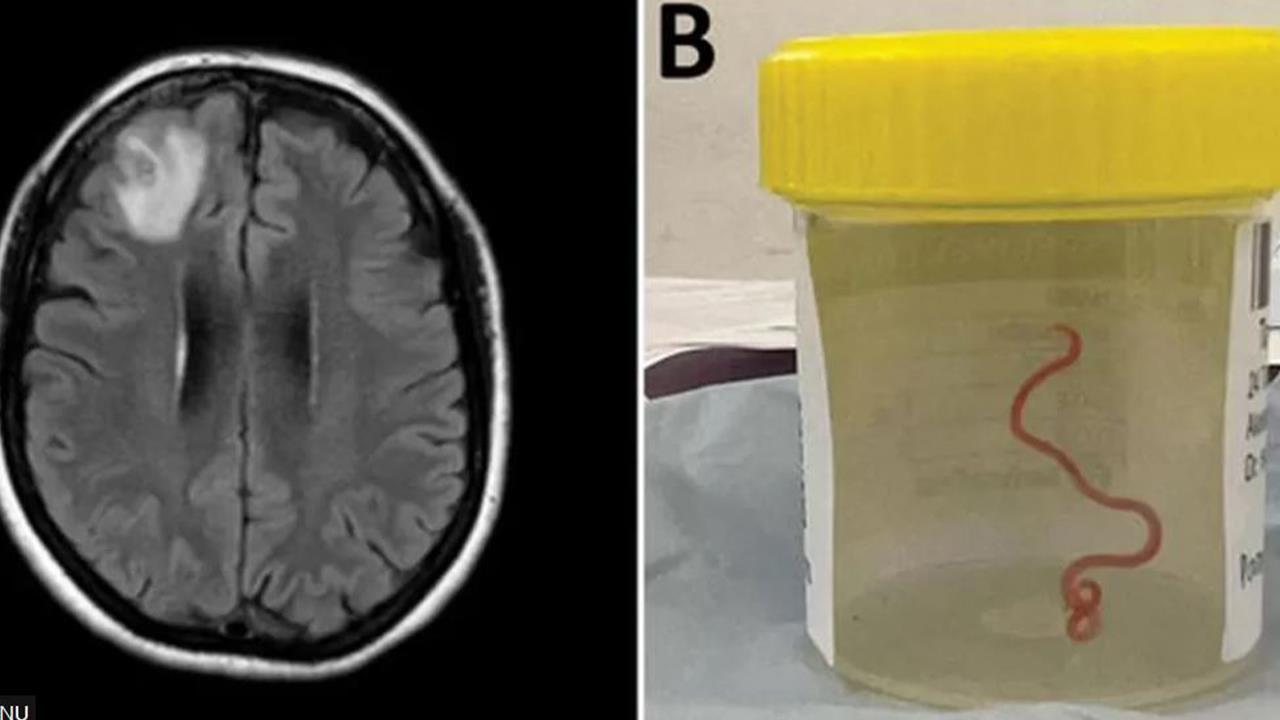

Για πρώτη φορά παγκοσμίως, επιστήμονες ανέφεραν πως βρήκαν ένα σκουλήκι 8 εκατοστών, ζωντανό στον εγκέφαλο γυναίκας στην Αυστραλία.

Η "εικόνα που μοιάζει με χορδή" τραβήχτηκε από τον κατεστραμμένο μετωπιαίο λοβό της ασθενούς κατά τη διάρκεια χειρουργικής επέμβασης στην Καμπέρα πέρυσι.

"Όλοι [σε] εκείνο το χειρουργείο έπαθαν το σοκ της ζωής τους όταν [ο χειρουργός] πήρε μερικές λαβίδες για να σηκώσει κάτι που θεώρησε ως μη φυσιολογικό και αποδείχθηκε ότι ήταν ένα ζωντανό, ανοιχτό κόκκινο σκουλήκι 8 εκατοστών", είπε ο Sanjaya Senanayake, λοιμωξιολόγος στο νοσοκομείο της Καμπέρα.

Ο ασθενής εισήχθη στο νοσοκομείο στα τέλη Ιανουαρίου 2021. Μια εξέταση αποκάλυψε «μία άτυπη βλάβη στον δεξιό μετωπιαίο λοβό του εγκεφάλου". Η αιτία της κατάστασής της αποκαλύφθηκε μόνο από το νυστέρι ενός χειρουργού κατά τη διάρκεια μιας βιοψίας τον Ιούνιο του 2022. Η γυναίκα αναρρώνει και είναι σε καλή κατάσταση.